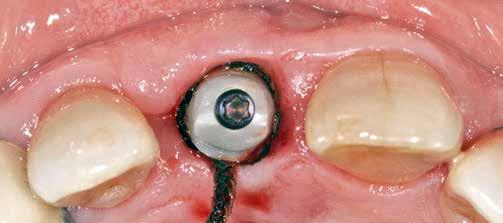

A korai harmicas éveiben járó hölgy rendelőnkbe érkezésének oka a jobb felső nagymetsző fog bizonytalan érzkenysége, elmondása alapján gyermekkorában trauma érte a felső frontrégiót. A frakturált klinikai koronákat kompozittöméssel helyreállították, egyéb kezelést akkor nem tartottak szükségesnek. Az utóbbi hónapokban tapasztalt érzékenység miatt kereste fel rendelőnket. A klinikai vizsgálat (1. és 2. kép) és a CBCT felvétel (3. kép) alapján diagnosztizált külső gyökérreszorpció megoldására a fog eltávolítását, implantátum

behelyezését, majd csavarozott rögzítésű, cirkónium-dioxid vázas, kerámialeplezésű korona készítését terveztük [1., 5., 6., 8.].

A tíz évvel ezelőtt még csak az állatkísérletekben leírt, azóta azonban már humán kutatásokban is vizsgált és napjainkban már széleskörűen alkalmazott, socket-shield technika alkalmazását tartottuk a legjobb választásnak [2., 4., 7.]. Az azóta megjelent szakirodalmi adatok alapján, a fent említett módszer alkalmas a bukkális oldal kemény- és lágyszöveti kontúrjának megőrzésére, a funkció mellett a megfelelő esztétikai eredmény elérésére is [3.].

A socket-shield technika lényege az azonnali implantációt megelőző részleges fogeltávolítás. Dekoronálást követően a megmaradt gyökér több darabban kerül eltávolításra, azonban a bukkális

falat mint „pajzsot”, meg kell őrizni, ezzel megelőzhető a bukkális csontfal egyébként fiziológiás reszorpciója (4. és 5. kép). A sebészi technika különös körültekintést követel meg, nehogy a bukkális „gyökérpajzs” megmozduljon, ezzel a bukkális oldalon megmaradt periodontális ligamentumok sérülését kockáztatnánk, amely az esetenként